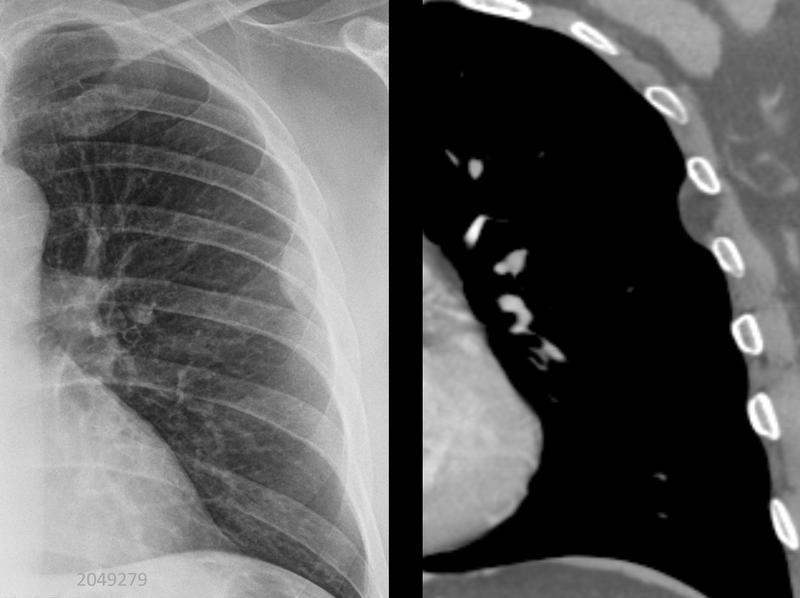

pleural lipoma